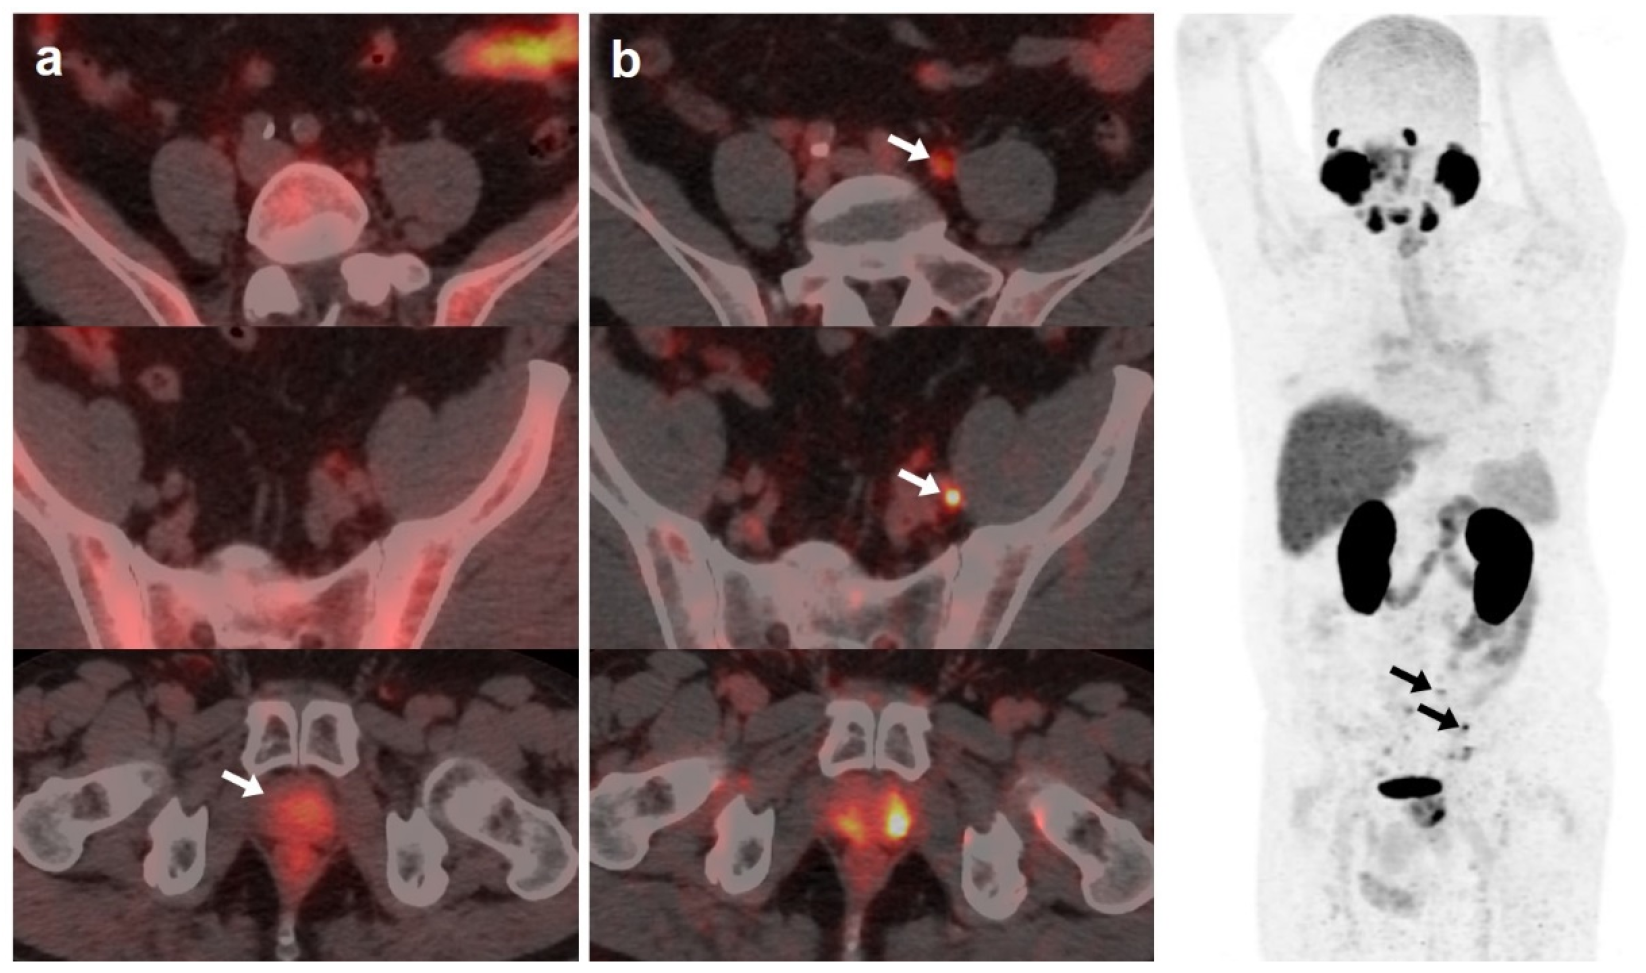

[18F]DCFPyL showed a higher DR than [18F]F-choline, 64.5% (89/138) and 33.3% (46/138), respectively. Both scans were negative in 44 patients (31.9%) and positive in 41 (29.7%). However, in 20/41 patients, [18F]DCFPyL visualized additional lesions compared with [18F]F-choline, which entailed miTNM stage change in 17 patients (Figure 1).

Figure 1.

59-year-old patient. Gleason 7 PCa treated with radiotherapy plus ADT. After ADT withdrawal BCR was detected (PSA 2.44 ng/mL, PSAdt 2.6 months, PSAvel 0.15 ng/mL/month). [18F]F-choline (a) demonstrated only prostatic uptake (white arrow) and [18F]DCFPyL-PET/CT (b) showed prostatic tracer uptake and lymph nodes metastases (white and black arrows). Time window of sixteen days between both scans. [18F]DCFPyL changed therapeutic management allowing escalation (ADT + Apalutamide).